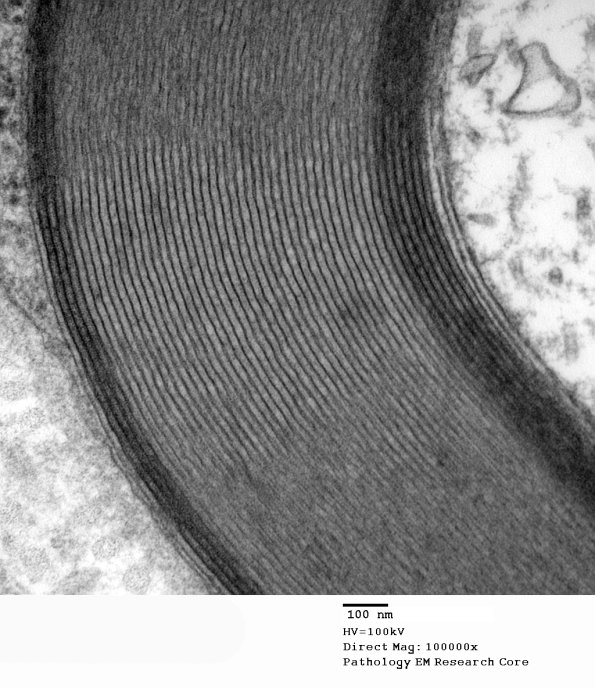

6A3 Two-tone myelin Paraprotein NP (Case 6)_048 - Copy

Higher magnification of image #6A2. (electron micrograph)